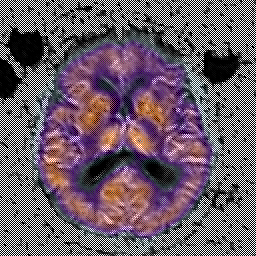

Alzheimer's Disease: SPECT/fMRI overlay -- Slice #5

[Home][Help][Clinical] Slice 5